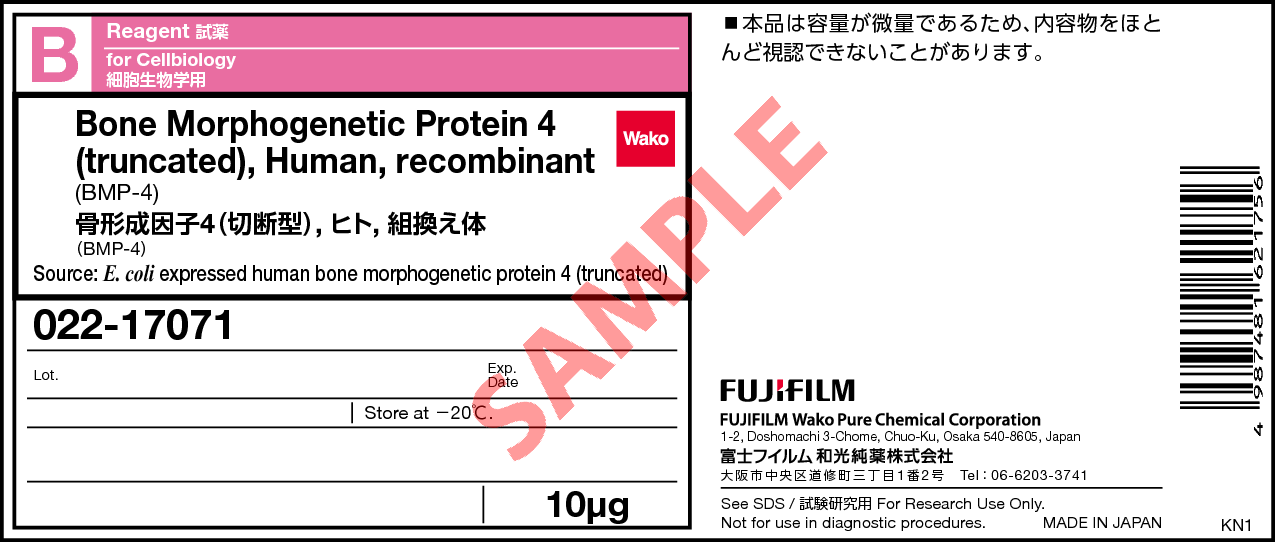

新核医学技術総論臨床編 | 日本核医学技術学会 |本 | 通販 | Amazon。日本核医学技術学会。心臓核医学の最新技術情報 - 技術解説 - シーメンス・ジャパン。茨城産10kg 精米 新米 コシヒカリ。購入時のコメントしないで下さいm(__)m随時価格を見直しておりますので値下げのお問合せはご遠慮下さいm(__)m大事なご連絡の見逃し防止のためお問い合わせ以外のメッセージ(挨拶、お礼、入金連絡等)はお控え下さいm(__)m\r\r【状態】\rカバーに使用感が少しありますが、中の紙面は良好な状態です。。骨形成因子4(切断型)(BMP-4), ヒト, 組換え体・Bone。\r\r【発送方法】\r基本1日おきに発送してますので最短お支払い当日、最長2日後発送です。循環器ジャーナル 6冊セット まとめ売り 医学書院 2017年 2018年 医学